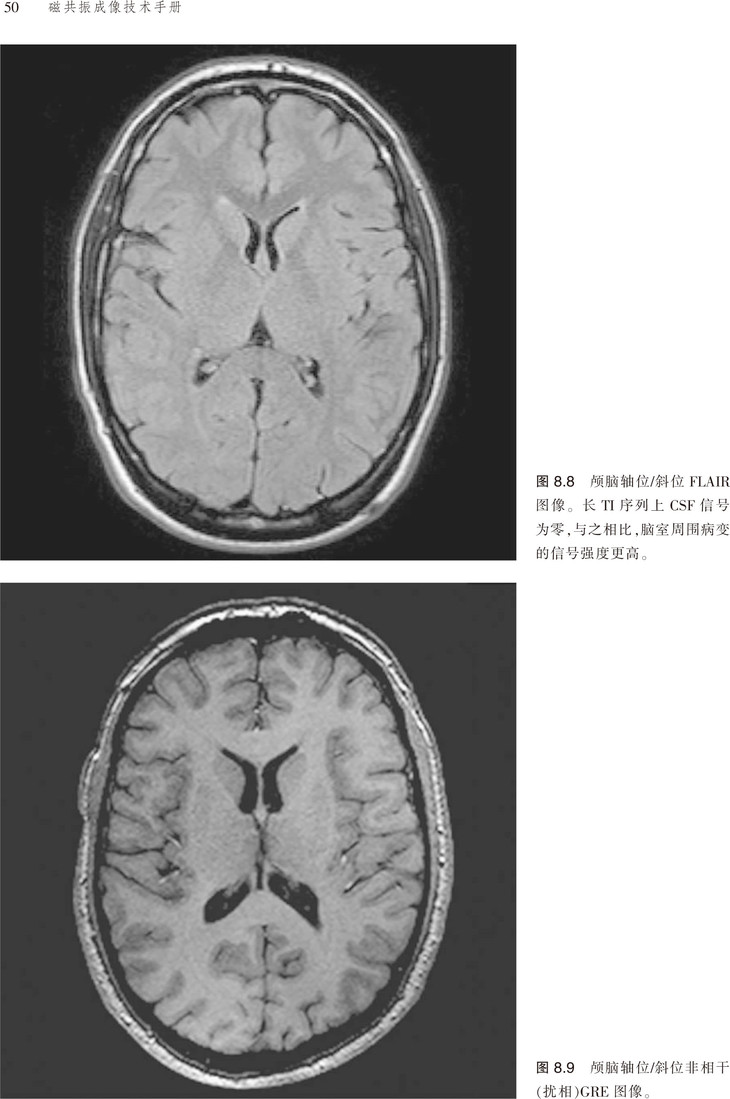

该书对脉冲序列、伪影、门控技术、预饱和技术等原理进行了讲解,且涵盖临床应用的相关参数,并就对比剂等以及受检者的安全性进行了分析。更为可贵的是该书不仅有应用解剖图谱,还有扫描的参照图,便于读者阅读,加深对书中内容的理解。